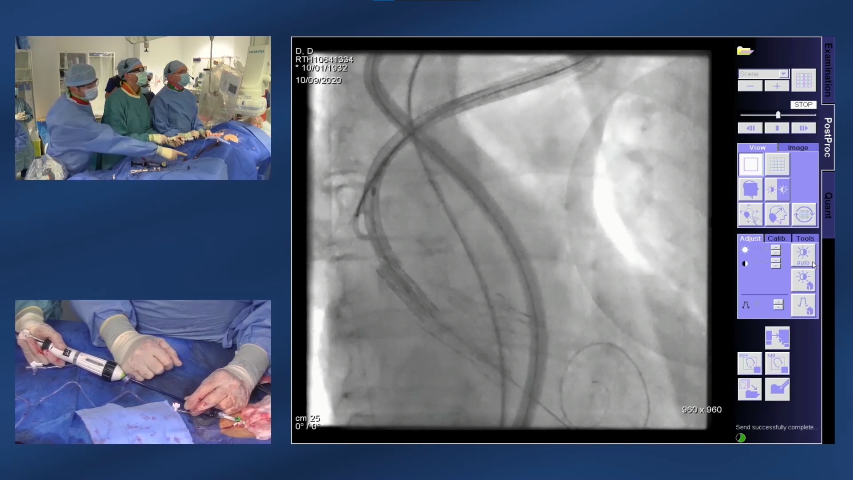

- La procedura TAVI ViV è simile a un intervento TAVI iniziale, in cui la valvola malfunzionante viene utilizzata per guidare il posizionamento della valvola sostitutiva6

- La valvola sostitutiva viene rilasciata gradualmente e la nuova valvola bioprotesica viene posizionata saldamente all’interno della valvola malfunzionante, schiacciando i vecchi lembi della valvola6

- Per garantire un posizionamento accurato della valvola viene utilizzata l’angiografia6